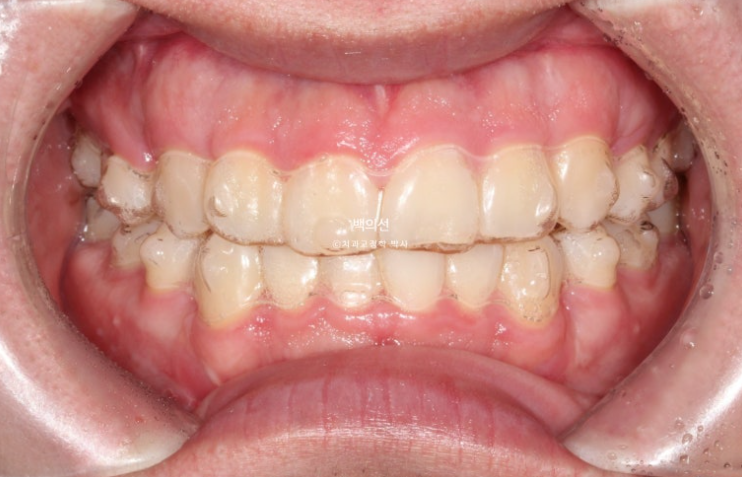

25.01

14개 장치를 다 낀 것은 25년 3월입니다.

25.03

교합 배열 모든 게 좋습니다만

아직 미세하게 남아있는 공간을 없애고자 추가장치를 제작하기로 했습니다.

25년 4월부터 8월까지 5개월간 14개 장치를 모두 낀 후 모습입니다.